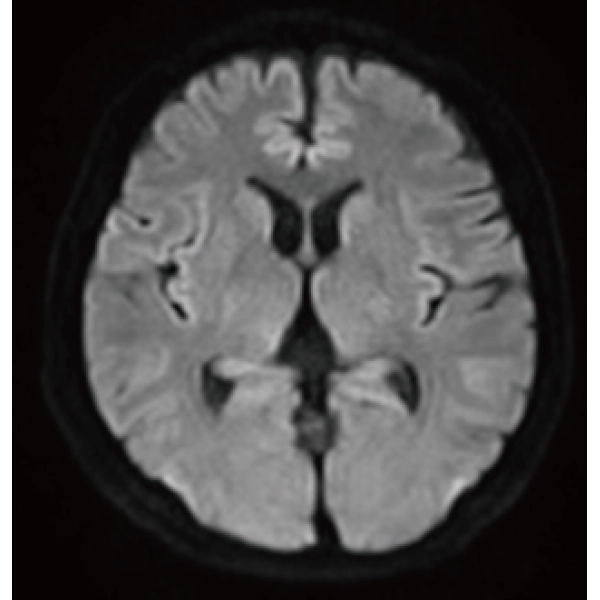

Deep Learning technology*8 enables image quality adjustment after imaging is complete. It optimize SNR and improve image sharpness by processing MRI signals in stages (k-space signal processing). This brings super-resolution and reduces truncation artifacts.